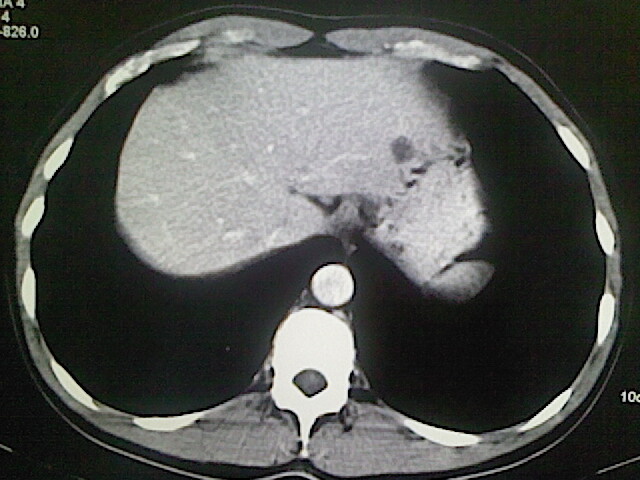

以下是引用卜一在2009-3-14 9:49:00的发言:[br]胆囊萎缩,胆囊壁不规则增厚,内部结构模糊,增强明显强化。另:肝左叶外侧段肝囊肿。支持:慢性胆囊炎!高度可疑:胆囊癌!

以下是引用余辉在2009-3-14 8:48:00的发言:[br]1)慢性胆囊炎。2)肝左叶外侧段肝囊肿。3)脂肪肝。[br]支持,胆囊萎缩,密度增高,不知b超具体有何提示,钙胆汁?结石?

以下是引用jiangjing在2009-3-14 10:18:00的发言:[br]1)慢性胆囊炎。2)肝左叶外侧段肝囊肿。3)脂肪肝。4.】建议行肝功能检查